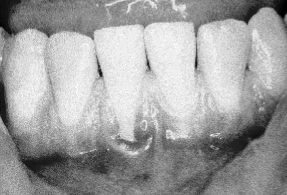

No standard method has been adopted to determine the buccolingual measurement. However, clinical observation is useful. Thin periodontal structures can easily be noted and differentiated from thicker ones. Prominent roots can be observed clinically. If the roots are quite prominent, one can see the roots directly below thin mucosal tissues since, adjacent to the mucosa or thin gingiva, no bone is present. In photograph #1, thin tissues can be seen on the facial aspects of teeth #23, 24, and 26. Gingival recession can also be observed on the facial aspect of tooth #25. Thin periodontal tissues in a buccolingual dimension may have predisposed tooth #25 to the development of gingival recession.

Photograph 1: Gingival recession, tooth #25